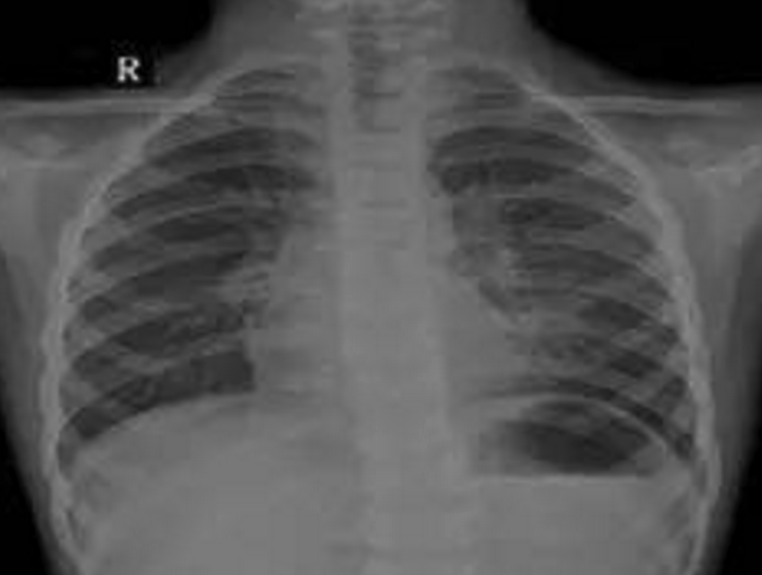

小文淵、小文博兄弟

2016年9月30日,39歲的徐士霞生下一對孿生寶寶孩子。然而孿生寶寶的降生只給這個家庭帶來了三天短暫的歡樂。10月2日,小文淵、小文博相繼出現抽搐、口吐白沫現象,齊齊哈爾第一醫院診斷為先天性心臟病,并發肺炎、肺衰竭、呼吸衰竭,雙雙住進重癥監護室。

5月11日下午,夫妻倆抱著文淵抵達上海兒童醫學中心,經過檢查,文淵重癥肺炎、重度支氣管炎,再不及時手術,會導致呼吸衰竭、心力衰竭。聽著醫生的診斷結果,夫妻倆泣不成聲,家里的文博情況比哥哥還要嚴重,治療費就像兩座大山一樣壓在了夫妻倆肩上。

據有關統計,先天性心臟病已經取代原來的唇腭裂、多指,成為了新生兒出生缺陷的病種,而且還在呈現上升趨勢,并成為導致5歲以下兒童死亡的首要原因。發病人數近10年增加了2.56倍,我國每年都將新增15萬~20萬先天性心臟病患兒,已經連續幾年成為新生兒、嬰幼兒時期死亡的主要原因。

有關數據顯示,35歲以上的高齡產下先天性心臟病嬰兒的幾率為25%。這主要是由于高齡產婦在懷孕時已經超過了較佳生育年齡,卵子在分裂的時候易發生染色體異常,導致胎兒患先天性心臟病的幾率增大。除此以外,遺傳因素,環境因素如孕期受到輻射、藥物影響、孕婦處于高原環境等也是產生胎兒先天性心臟病的重要原因。